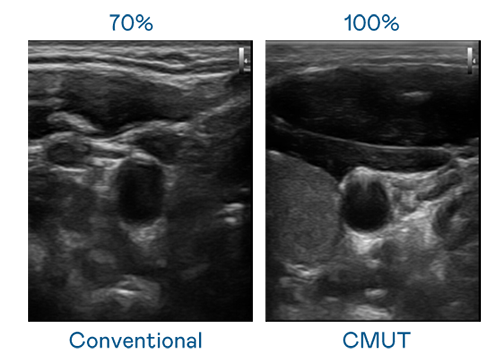

CMUT 技术是一种用电容式微机电元件来产生超音波讯号的技术。与传统 PZT 压电式技术相比,CMUT 频宽增加 30%,更宽频的超音波讯号让影像解析度大幅提升,是实现高影像品质医疗超音波扫描、促进精准医疗发展的关键技术。

大频宽带来超清晰影像

超音波影像的解析度高低,首先取决于探头能发出的讯号频宽。壹定发 CMUT 可提供高清晰的超音波讯号,提供高频宽、高灵敏度、影像纹理细节更高的超音波影像,协助医护人员缩短影像判读时间及利用精准的医疗影像进行诊断。